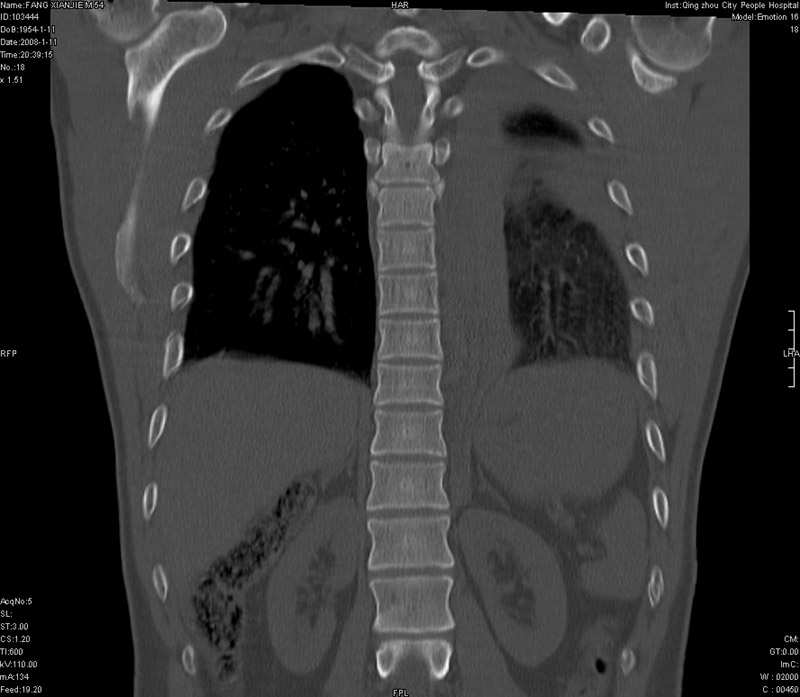

男性,40岁。胸部被车压伤伴胸痛1小时来院就诊。检查:一般情况尚可,血压110/80,胸部及上腹部压痛。结果在三天后公布。骨窗在横断位、冠矢状显示肋骨、胸椎、和胸骨未见骨折征象。

纵隔血肿,大血管破裂?左侧胸腔积血,胸骨柄骨折,冠状位示双侧第三肋骨折.

2、胸骨柄骨折,冠状位示双侧第三肋骨折.

ct11308:胸部外伤1小时(证实病例) (2008-1-13 16:2)结果如下:病人入院后两小时后症状加重,8小时后在征得病人家属同意做了ct增强扫描。如下图。最终临床诊断:外伤性胸主动脉破裂并纵隔内血肿。由于有运动性伪影,胸骨在矢状面重建的图像似有骨折征,这是一种假象,我们称之为“假骨折”,这在多层ct重建中经常性遇到,必要时要结合横断图像鉴别之。现在,病人的一般情况较差,是否要手术家属尚有争议,如果手术修补,难度较大,需要专门预定制作固定支架。

以下是引用拾荒者在2008-1-16 18:46:00的发言:[br]ct11308:胸部外伤1小时(证实病例) (2008-1-13 16:2)结果如下:病人入院后两小时后症状加重,8小时后在征得病人家属同意做了ct增强扫描。如下图。最终临床诊断:外伤性胸主动脉破裂并纵隔内血肿。由于有运动性伪影,胸骨在矢状面重建的图像似有骨折征,这是一种假象,我们称之为“假骨折”,还有双侧肋骨的“假骨折”,这在多层ct重建中经常性遇到,必要时要结合横断图像鉴别之。现在,病人的一般情况较差,是否要手术家属尚有争议,如果手术修补,难度较大,需要专门预定制作固定支架。[br][br]再次表示感谢!

当然,对于该病例,其它非重要的诊断还有:右侧少量气胸;左侧胸腔积液;左侧轻度肺挫裂伤。对于纵隔内血肿,我们曾经遇到过多例,也有怀疑主动脉的破裂,但是,均未得到具体出血部位的明确诊断。